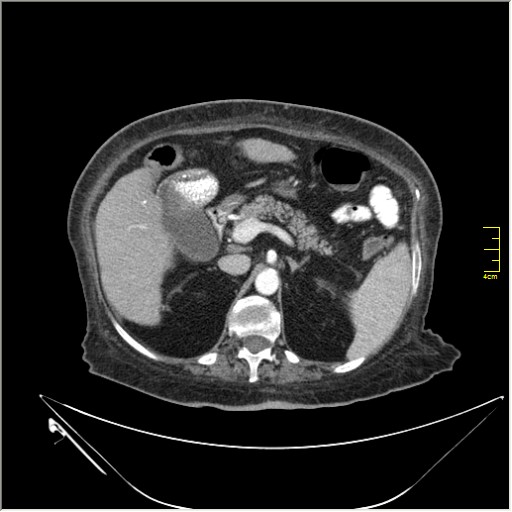

Весьма актуальная тема. Часто при проведении КТ исследования по тому или иному поводу, мы находим патологию, никак не связанную с клиникой пациента и не являющимся причиной обращения в кабинет КТ. Очень важно знать; как с этим быть, какие рекоммендации и действия необходимо предпринять. Для примера приведу одно наблюдение.

N.B. Все "находки" никак не были связаны с клиникой.

Находки 2:

1.Образование правого надпочечника с плотностью жира, липома. Ничего делать не надо. По другим вариантам incidentalomas, Др. Капустин всё расписал.

2. Множество мелких конкрементов жёлчного пузыря, заполняющие до 50% просвета. С этим надо что-то делать. )))